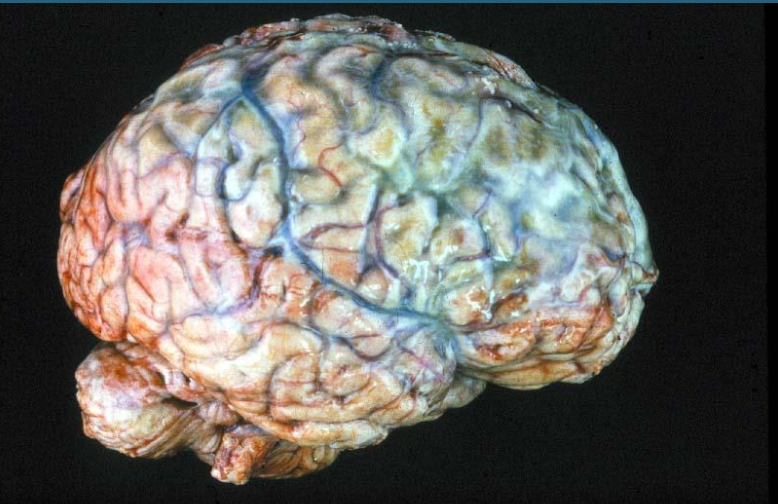

11

A

Bacterial meningitis